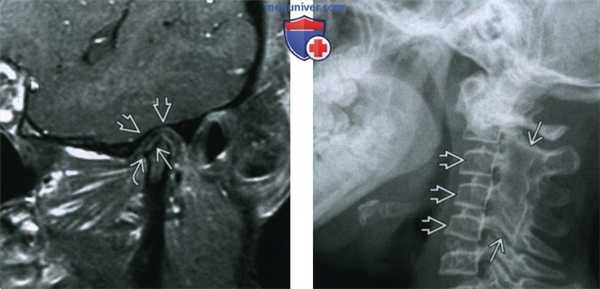

(Слева) На рисунке ВНЧС при РА изображен паннус в суставном пространстве, разрушающий костную ткань мыщелка и суставного возвышения, и смещающий связки заднего полюса суставного дискам.

(Справа) На Т1 МРТ ВНЧС у пациента с РА определяется уплощение верхней поверхности мыщелка и заднего края суставного возвышения с наличием эрозий. Губчатое вещество мыщелкового отростка имеет гипоинтенсивный сигнал. Объемное образование с промежуточным сигналом возле мыщелка представляет собой паннус Обратите внимание на смещение связки, прикрепляющей задний полюс диска к височной кости, книзу. (Слева) На Т1 МРТ(с закрытым ртом) у пациента с РА определяется эрозия верхней поверхности мыщелка В визуализируется объемное образование с промежуточным сигналом, подозрительное на паннус, приводящее к расширению обоих отделов сустава.

(Справа) На Т1 МРТ ВНЧС (с открытым ртом) у этот же пациента определяется уменьшение размеров мыщелка вдоль ею задней поверхности. Объемное образование с промежуточным сигналом, подозрительное на паннус, обусловливает расширение обоих от делов сустава. Диск не визуализируется. (Слева) На сагиттальной КТ у пациента с РА определяются эрозии заднего края зубовидного отростка. Переднее атланто-дентальное пространство (ПАДП) расширено.